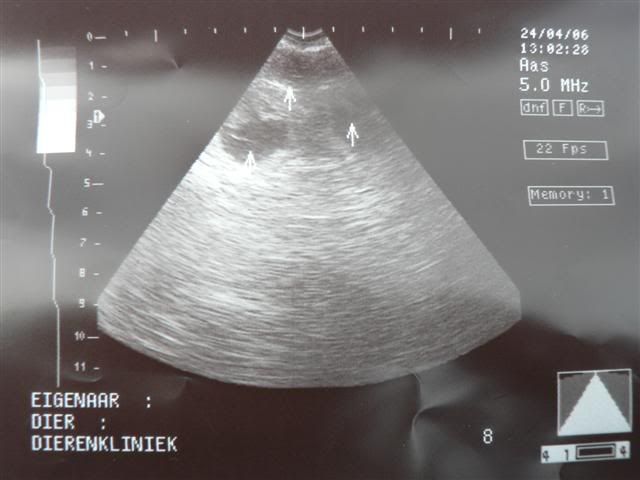

Vandaag, op de sterfdag van Bolletje zagen we op de echo dat Pientje puppies krijgt. Er waren er 5 heel goed te zien. Over het aantal kon ze moeilijk iets zeggen omdat ze verlegen waren en zich achter elkaar verscholen. Het zal geen supergroot nest worden maar de dierenarts verbaast zich nergens meer over......

Pien is op 27 mei uitgerekend, dat is dan 63 dagen na de 2e dekking.